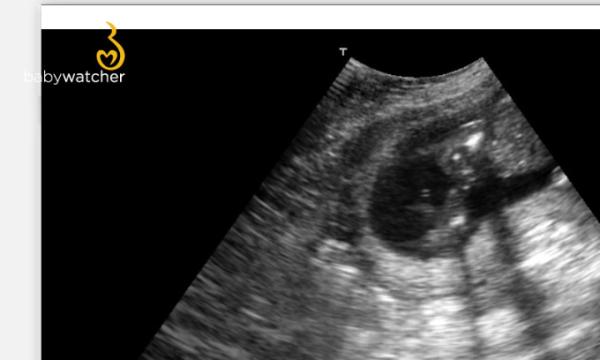

Hier Mal ein Bild

Das ist der Babywatcher. Den kann man sich im Internet mieten und dann zu Hause selber Ultraschall machen. Ich find das Teil einfach Klasse. Hier Mal ein Bild von heute,meint ihr man kann da erkennen was es wird? Ist von hinten das Bild. Es zeigt uns quasi den Po LG julienmami